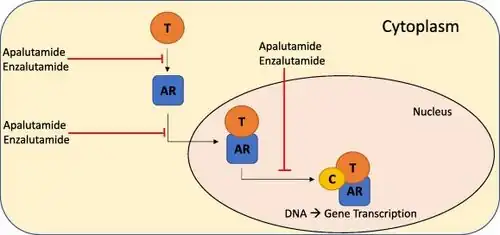

Prostate cancer that persists when testosterone levels are lowered by hormonal therapy is called castrate-resistant prostate cancer (CRPC).[136][137] Many early-stage cancers need normal levels of testosterone to grow, but CRPC does not. Previously considered "hormone-refractory prostate cancer" or "androgen-independent prostate cancer", the term CRPC emerged because these cancers show reliance upon hormones, particularly testosterone, for androgen receptor activation.[138]

Immunotherapy treatment with sipuleucel-T in CRPC increases survival by four months.[143] The second line hormonal therapy abiraterone increases survival by 4.6 months.[144] Enzalutamide is another second line hormonal agent with a five month survival advantage. Both abiraterone and enzalutamide are currently in clinical trials in those with CRPC who have not previously received chemotherapy.[145][146]

All medications for CRPC block AR signaling via direct or indirect targeting of the AR ligand binding domain (LBD). Over the last decade molecules that could successfully target these alternative domains have emerged.[217] Such therapies could provide an advantage; particularly in treating prostate cancers that are resistant to current therapies like enzalutamide.[217]